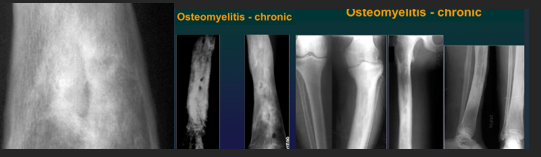

CharaK Osteomyelitis

Chronic, evolution in bursts

Single bone, single place

Involves etaphyses an diaphyssis NOT epiphysis NOR joints

Xray CharaK

Bone sequestration

Osteosclerosis

Periostosis

Hyperostosis

Chronic Osteomyelitis MRI

Active foci

Abscess

Fibrosis

Sequestration

Soft tissue abscess

Chronic Osteomyelitis CT

Cortcal thinnign

Fistulae (fistulography)

Soft tissue absecess (+ contrast)